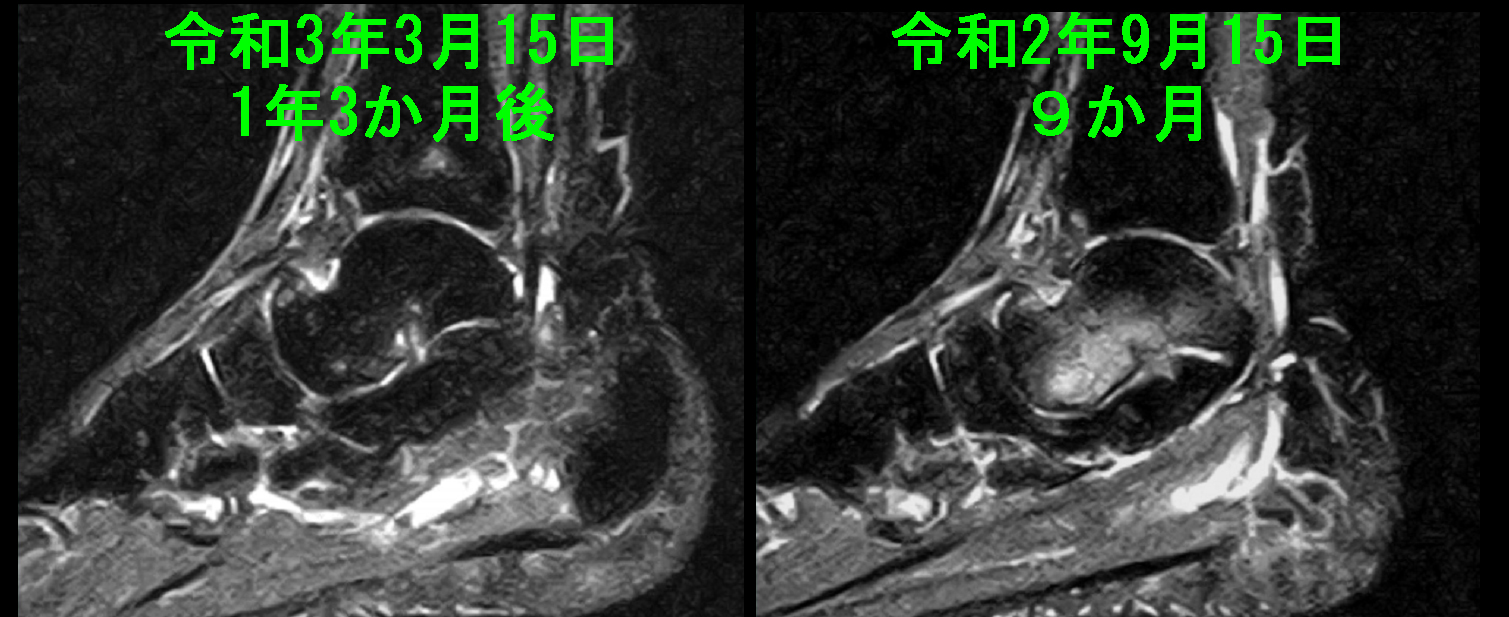

31才男 初診時MR4.jpg

経過中には右距骨の炎症所見も発症していますが、治療経過で軽減が確認されています。